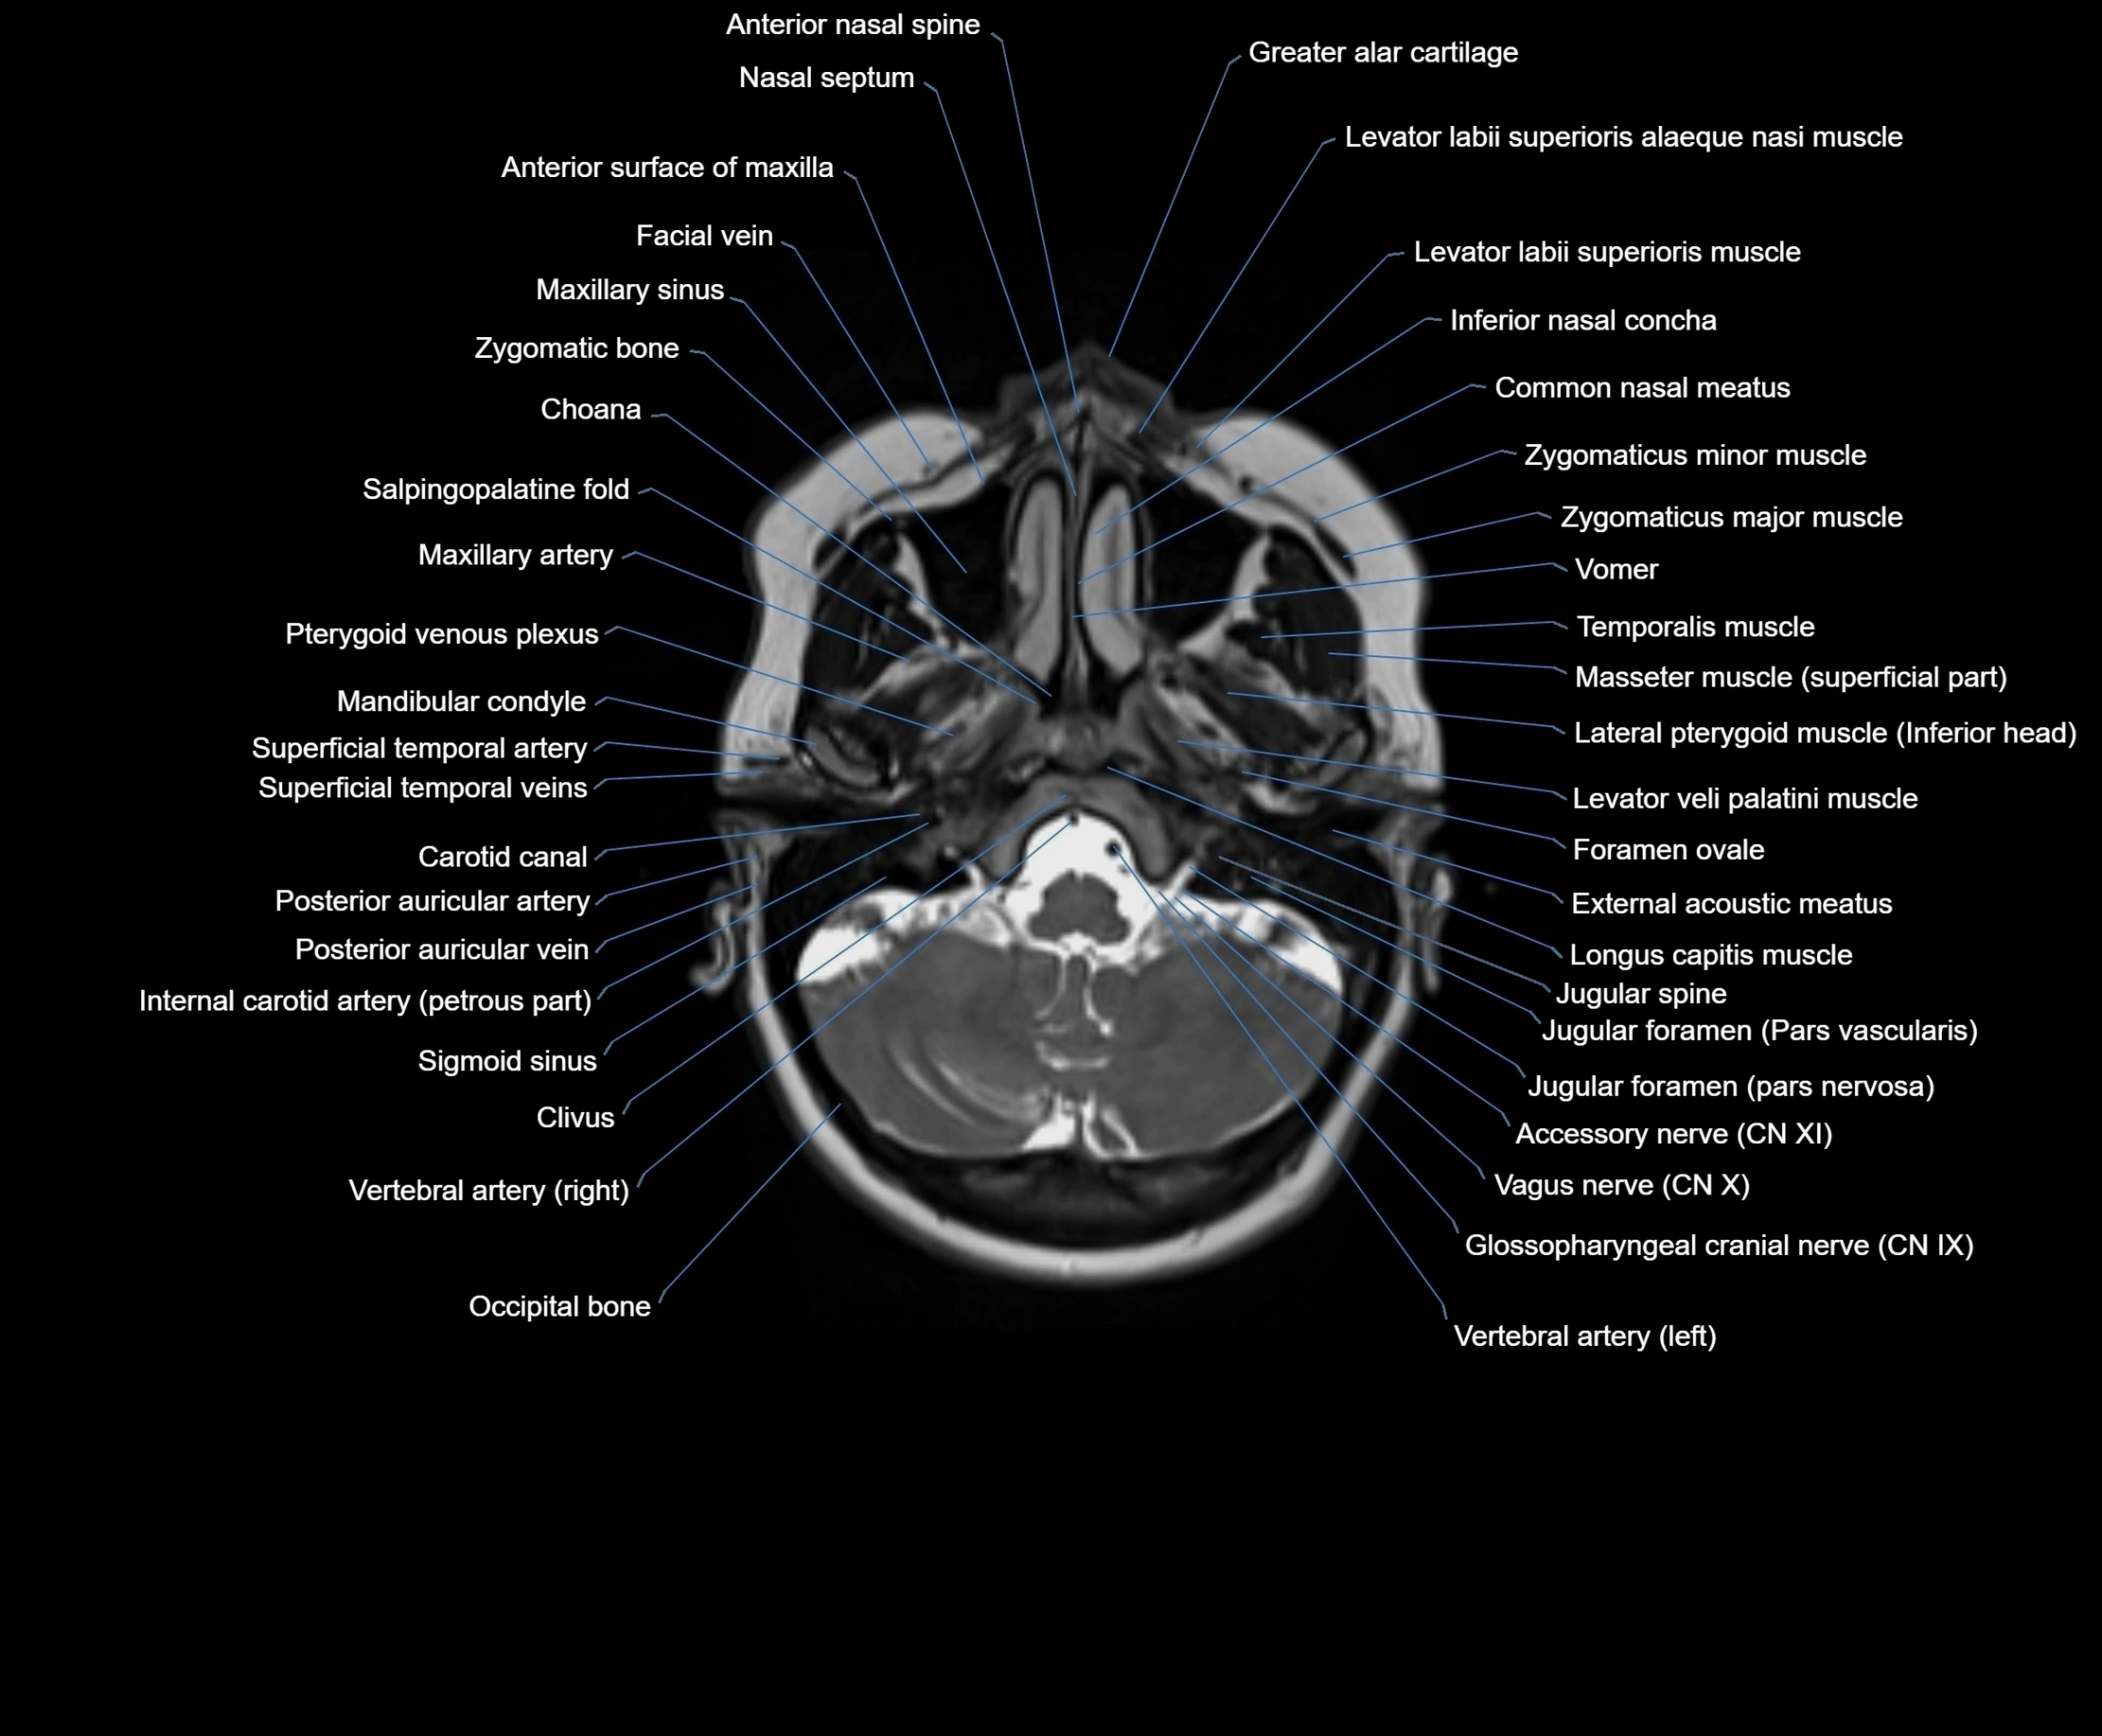

- Anterior nasal spine

- Body of sternum

- Carotid canal

- Choana

- Clivus

- Common nasal meatus

- External acoustic meatus

- Facial vein

- Foramen ovale

- Glossopharyngeal nerve (Cranial nerve IX)

- Greater alar cartilage

- Inferior nasal concha

- Internal carotid artery (petrous part)

- Internal occipital crest

- Jugular foramen

- Levator labii superioris alaeque nasi muscle

- Levator labii superioris muscle

- Levator veli palatini muscle

- Mandibular condyle

- Maxillary artery

- Maxillary sinus

- Occipital bone

- Posterior auricular artery

- Posterior auricular vein

- Pterygoid venous plexus

- Salpingopalatine fold

- Superficial temporal artery

- Superficial temporal vein

- Vagus nerve (Cranial nerve X)

- Vomer

- Zygomatic bone

- Zygomaticus major muscle

- Zygomaticus minor muscle